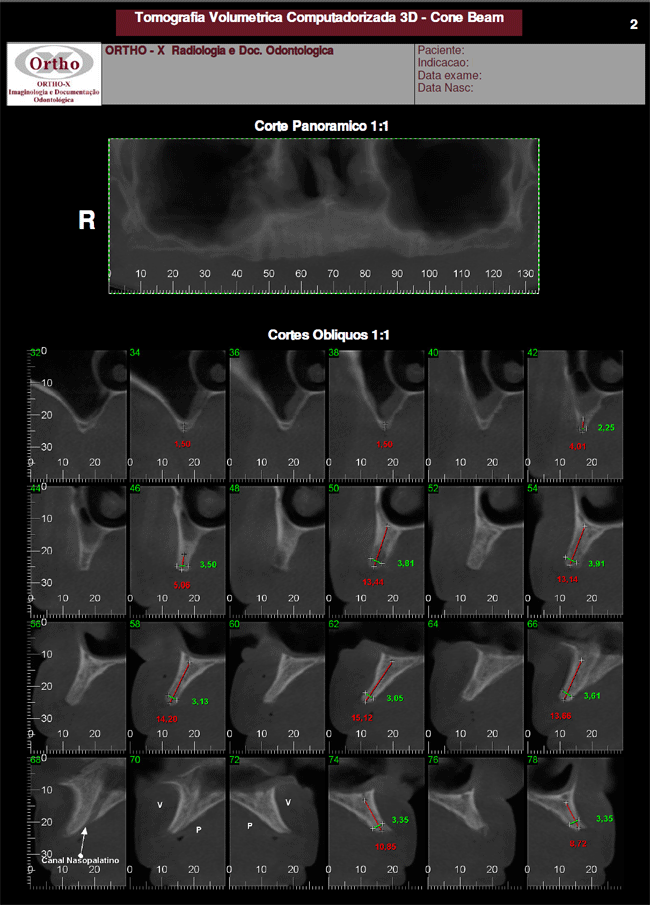

A tomografia CONE BEAM é um exame de alta resolução que é capaz de analisar os dentes e suas estruturas ósseas vizinhas em três dimensões. É permitida a avaliação de mensurações da altura, largura e profundidade das estruturas, o que não é possível com os exames radiográficos convencionais. Estas informações proporcionam mais segurança para os procedimentos, aumentando os índices de sucesso terapêutico.